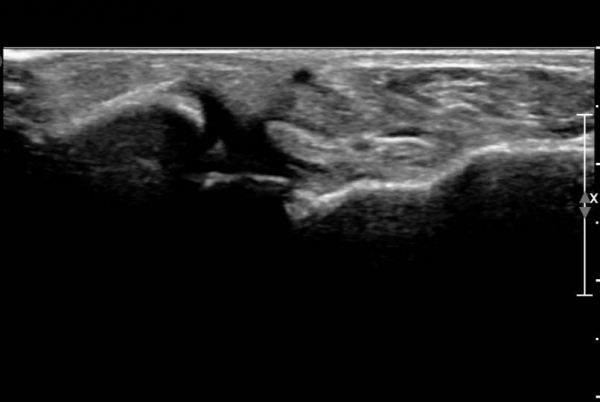

¾Õ°æ°ñºñ°ñÀδë Á¾´Ü¸é°Ë»ç¿¡¼­ °æ°ñºñ°ñÀδëÀÇ  Àú¿¡ÄÚ  ºÎÁ¾ ¹× ÀδëºÎÂøºÎ °æ°ñÀÇ

°ß¿­°ñÀýÀÌ  °üÂûµÊ(»çÁø 2, 3, 4)